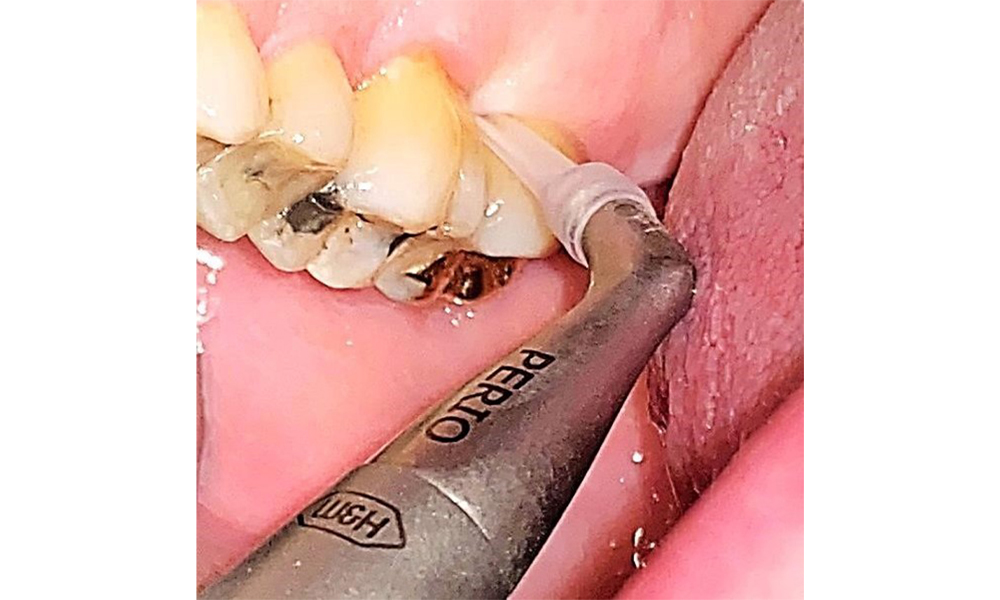

Supragingival and subgingival biofilm removal is indispensable for maintaining the stability of the periodontal condition. Air polishing using low-abrasive powder is suitable for this purpose. Periodontal pockets and exposed root surfaces must be cleaned with low-abrasion powders. The use of a flexible parotip is recommended for patients with increased probing depths (deeper than 5 mm) (Fig. 10). (9)

Subgingival application of the flexible air polisher tip (Proxeo Aura, W&H, shown here) to the mesiopalatal aspect of tooth 27 with a periodontal pocket depth of 5 mm.

Fig. 10: Subgingival application of the flexible air polisher tip (Proxeo Aura, W&H, shown here) to the mesiopalatal aspect of tooth 27 with a periodontal pocket depth of 5 mm. © Dr R. Krapf